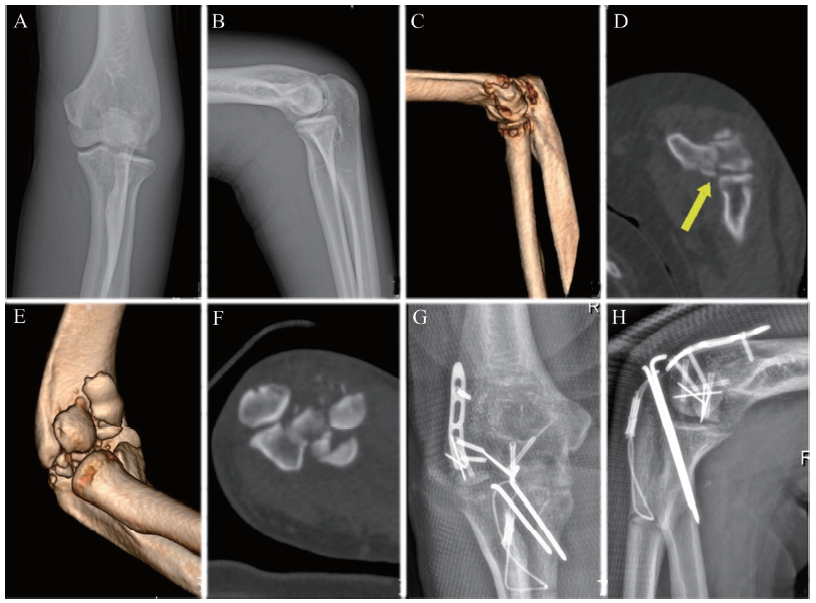

15例实施手术时间为伤后26(21 ~ 36) d,导致骨折延误治疗的原因包括:5例因早期症状不重而贻误就诊时间,5例因骨折碎裂严重而辗转多家医院就诊致延误手术,3例早期保守治疗处置不当,2例因症状不明显而早期漏诊。典型病例影像学检查图片见图1

图1 陈旧性肱骨远端冠状面骨折典型病例影像学检查图

A ~ D:病例1,患者女,59岁,行走时滑倒摔伤左肘,Dubberley分型为ⅡA型,早期临床症状轻而被漏诊致进展为陈旧性骨折。A、B为受伤当日正侧位X线片,仅显示肱骨远端骨质密度改变,无典型的半月影、双弧征表现,故未进一步行CT检查;C、D为受伤后23 d 的CT三维重建片,箭头处显示肱骨小头冠状面骨折,断端移位。E ~ H:病例2,患者男,38 岁,跑步时跌倒摔伤右肘,Dubberley分型为ⅢB型,因辗转多家医院而延误手术致进展为陈旧性骨折。E、F为受伤后25 d CT三维重建片,显示骨折碎裂严重,可见骨折端移位明显,肱骨远端后壁亦碎裂;G、H为术后第3日正侧位X线片,显示骨折复位良好